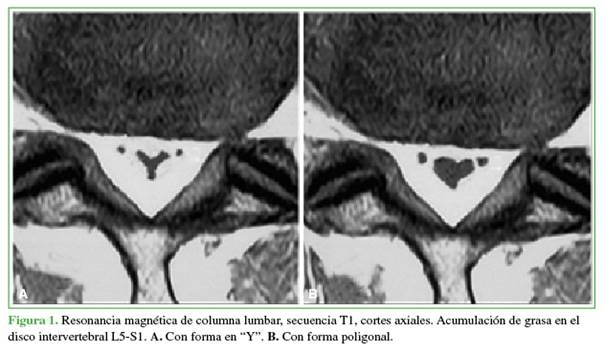

El estudio de elección para el diagnóstico es la resonancia magnética (RM), las imágenes típicamente muestran un tejido en el espacio epidural posterior hiperintenso en la secuencia T1, señal intermedia en la secuencia T2 e hiposeñal con supresión grasa, como característico del tejido graso.14,20-23 La imagen típica en el corte axial fue descrita por Kuhn y cols.2 como el signo de la “Y” por compresión circunferencial del saco dural a nivel lumbar. Borré y cols.,8 y Naka y cols.21 proponen distintos grados para la LEE, donde el grado III es el más severo, sintomático y suele observarse esa imagen en “Y” característica (Figuras 1 y 2).

Existen diversas graduaciones según las imágenes de la RM, pero ninguna se correlaciona con las manifestaciones clínicas.2,8,20-22 Borré y cols.8 proponen una clasificación de la LEE en las imágenes de la RM de 0 a III según el porcentaje del canal vertebral ocupado por el tejido graso; el grado III es siempre sintomático (con una ocupación del canal >70%). Naka utiliza cortes axiales y sagitales de RM para la clasificación de 0 a III, las formas avanzadas se asocian con la imagen en “Y” descrita por Kuhn y cols.2